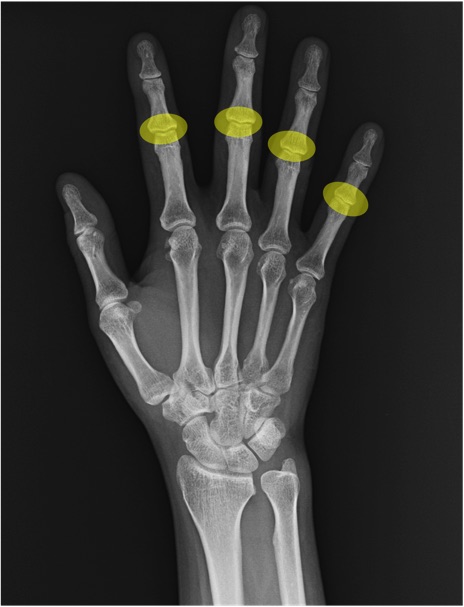

PIP関節(proximal interphalangeal joint)の手関節レントゲン画像における正常解剖

基節骨(proximal phalanx)

MP関節(metacarpophalangeal joint)